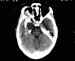

Figura 4. Las leucemias infiltran el globo ocular, nervio óptico y

órbita en varias manifestaciones.